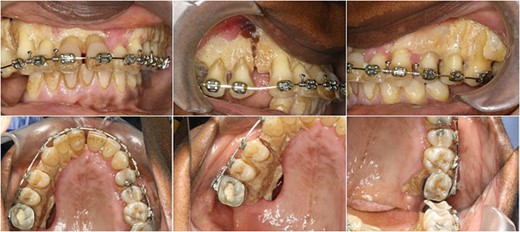

Preoperative orthopantomograph showing expansion of the right maxillary tuberosity.

The operation planned was a Le Fort I osteotomy with a right posterior segment osteotomy, which would set back the upper incisors by 6 mm, impact the upper left second molar by 4 mm and impact the posterior segment from the upper right first premolar (by 5 mm) to the upper right first molar (by 12 mm). No forward movement of the maxilla was planned. The segmental osteotomy was performed following down fracture of the maxilla and the final occlusion was aligned to a full coverage occlusal splint. The right descending palatal artery was sacrificed.

The maxillary mucosa appeared pale during the procedure, but showed capillary refill. The patient presented with wound infection and avascularity of the maxilla 1 week after the procedure. She was treated with intravenous Co-amoxiclav for 2 weeks. A course of hyperbaric oxygen treatment was organized at 14 and 18 days post-operatively. She was started on therapeutic doses of Pentoxyfylline and Vitamin E to improve capillary blood flow.